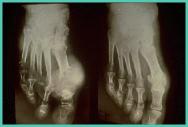

痛风石,又称痛风结节,是痛风患者在疾病发展过程中在关节处生长、凸起的一个包块或者疙瘩。它是人体内因血尿酸过度升高,析出的白色晶体堆积而形成的,一般痛风病史5年的患者都会慢慢形成痛风石。

痛风石逐渐增大后,其外表皮肤可能变薄溃破,形成窦道,排出白色牙膏样的尿酸盐结晶物,经久不愈。发生在手足附近的结石,常影响关节活动,导致慢性关节肿痛、僵直和畸形, 甚至骨折。

一般来说,在身体表面的痛风石,通过饮食调节或是药物治疗,能被溶解的可能性非常小。对于痛风石,一般出现骨、软骨组织破坏甚至皮肤破溃时,单纯应用药物治疗极少有治愈者。适时的外科手段介入可缓解症状,解除压迫并矫正畸形,及时阻断其病程,改善肢体功能,减轻机体尿酸负荷,有利于提高患者的生活质量和功能的改善。